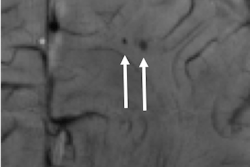

The researchers used the high-resolution T2-weighted TSE images most frequently for their initial detection of subtle structural abnormalities, while the SWI sequence was "highly sensitive for the detection of focal susceptibility changes caused by or associated with cortical defects, cavernomas, and [developmental venous anomalies]," they wrote.

Feldman and colleagues found 25 potentially epileptogenic abnormalities (67%) with 7-tesla MRI in the 37 patients with focal epilepsy; the abnormalities were not seen on lower-field MR images. The lesions were "definitely" or "likely" related to epilepsy in eight patients (21%). The detection of seven abnormalities (19%) directly changed the course of patients' surgical intervention and treatment planning.